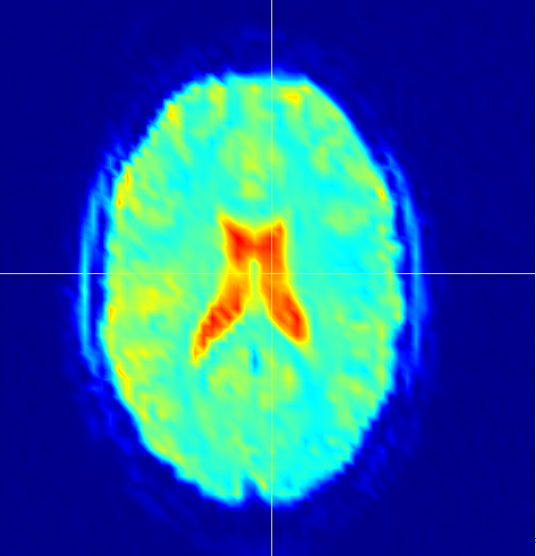

fMRI brain scan data sets are inherently four-dimensional, so unwrapping the dataset into a two-dimensional array creates a tall-skinny matrix with hundreds of times more rows than columns. The enormity of these data sets makes low-rank recovery models intractable without parallelization. Figure 11 shows the total time spent performing SPCP on one of these data sets, as well as the total time spent performing rSVDs, performing the QR step of the rSVD, and moving data (labeled as the “overhead” cost). The results of this test are included in Figures 12 and 13.

The datasets used for testing were taken from a study of the human brain’s response to uncomfortable stimuli, specifically, the feeling of submerging a hand in hot or cold water. Analyzing these scans to find common neurological responses to these stimuli is difficult due to the enormous amount of error in the data. There is uniformly distributed noise due to constant ancillary physiological activity, and there are also sparsely distributed groups representing neurological structures that should all exhibit the same behavior. The ventricles, for example, are filled with cerebrospinal fluid (CSF), which does not contribute to neurological communication, so they should not be active. All signals observed in the ventricles should be treated as sparsely structured outliers. SPCP removes the uniform noise and, most remarkably, correctly identifies signals in the brain’s ventricles as outliers. In Figure 12, the largest ventricles are the two structures in the center of the brain. The rightmost image shows that the majority of the noise contained in is from these ventricles.

The other two major components of the brain are white and gray matter. The activity we are hoping to observe takes place in the gray matter, so ideally SPCP would remove most signals from the white matter regions. However, the regions of white matter are more difficult to distinguish than the regions of CSF, and SPCP removes about equal amounts of noise from the white matter as it does from the gray. If we let be the gray-matter component of , and define and similarly, Figure 13 shows the average BOLD signal in , and for each frame in time. These data were normalized by the average original signal in the corresponding regions.

It is clear that contains more signal than the other two regions. For , SPCP detects noise in only the first 100 time slices. The removed signal from the white matter is more distributed over time, and the total amount of noise in and is comparable. These results suggest that SPCP correctly identifies outliers in the fMRI data, especially within the regions of CSF.